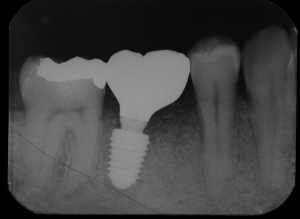

根が折れて骨が吸収した奥歯をインプラントで治療した症例

頻繁に奥歯のまわりが腫れてくるとのことでご来院されました。初診時は応急的に抗菌薬で炎症を抑えて、後日現状を詳しく精査していきました。2本あるうちの手前の1本の根っこが縦に割れてしまっている状態でした。…